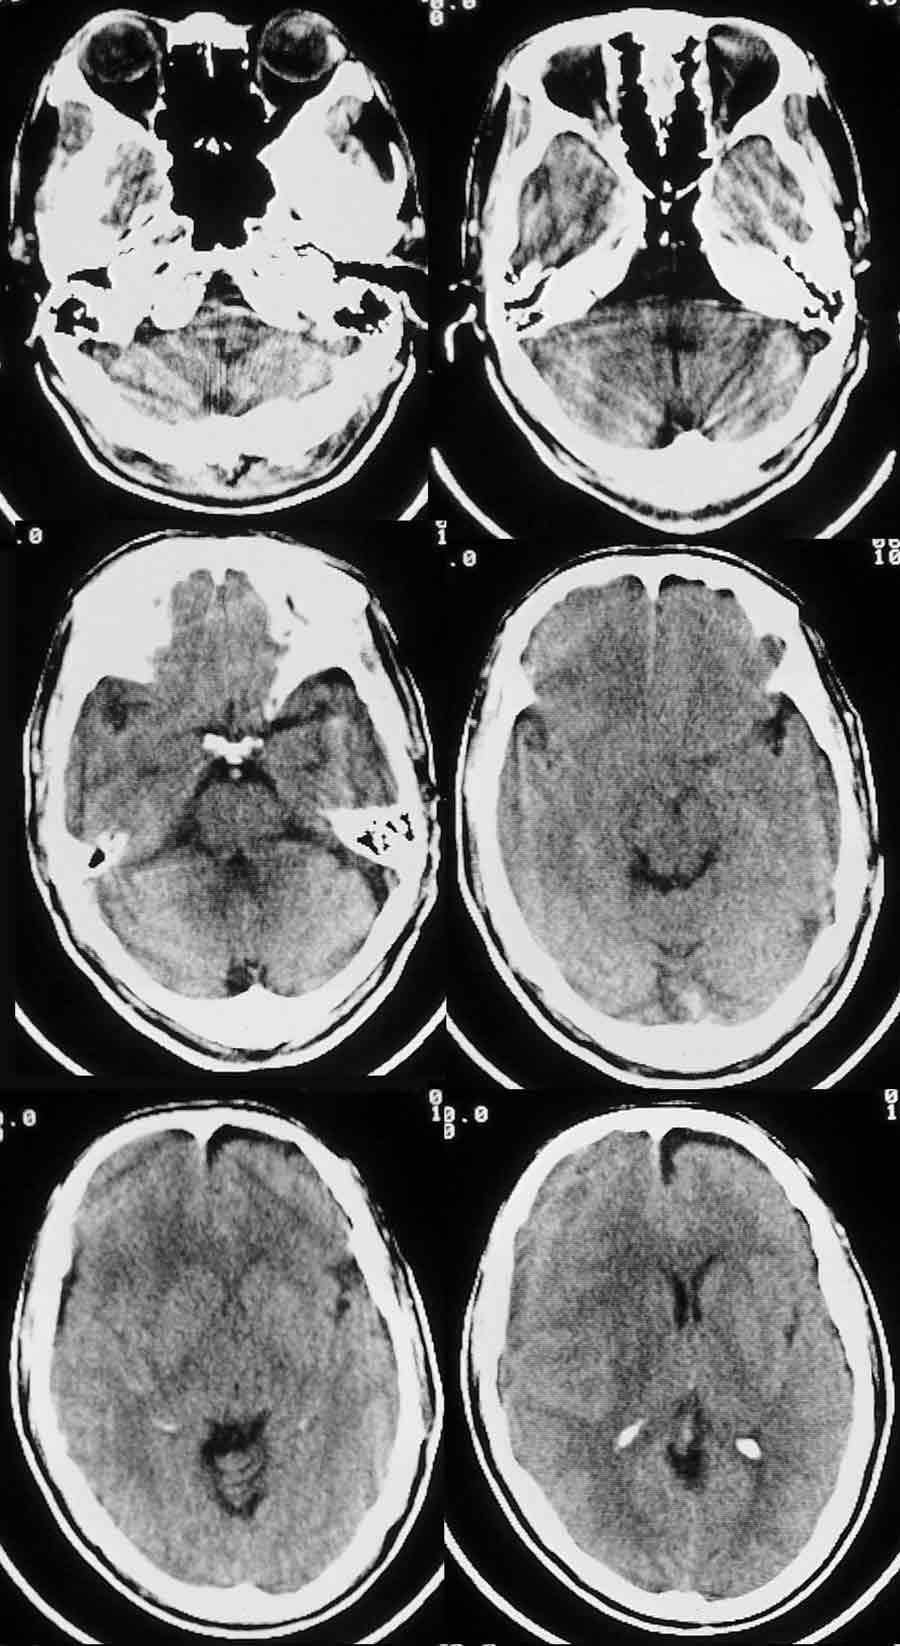

m/63岁,以左侧肢体麻木一周就诊;

右侧外侧裂、右侧脑沟均较窄,右侧灰白质均向左移位,中线结构亦左移。右侧颅板下见与皮层等或略低密度的条形影。

考虑:右侧亚急性硬膜下血肿。

右侧脑沟裂消失,皮髓质交界点内移,右侧脑室受压,慢性硬膜下血肿

1右额颞顶部慢性硬膜下血肿,2左硬膜下积液

右侧额';,颞,顶颅骨内板下可见弧低密度影,脑灰质移位,右侧外侧裂池及侧脑室,大脑半球脑沟变窄,应该是个慢性硬膜下血肿

左额叶慢性硬膜下积液

1、右侧额颞部亚急性硬膜下血肿 2、左侧额部硬膜下积叶

右侧额顶亚急性硬膜下血肿,等密度

有些硬膜下出血特别是老人多表现为等或略低密度,有时不易辨别,需用窄窗技术观察,大家平时工作中要提高警惕!

诊断:右侧亚急性慢性硬膜下血肿

补充:左侧额叶前边低密度考虑是硬膜下积液,对应脑组织有受压变圆钝,脑回消失;左侧顶叶低密度考虑是局限性脑萎缩 ,局部脑回正常,脑组织无受压迹象。